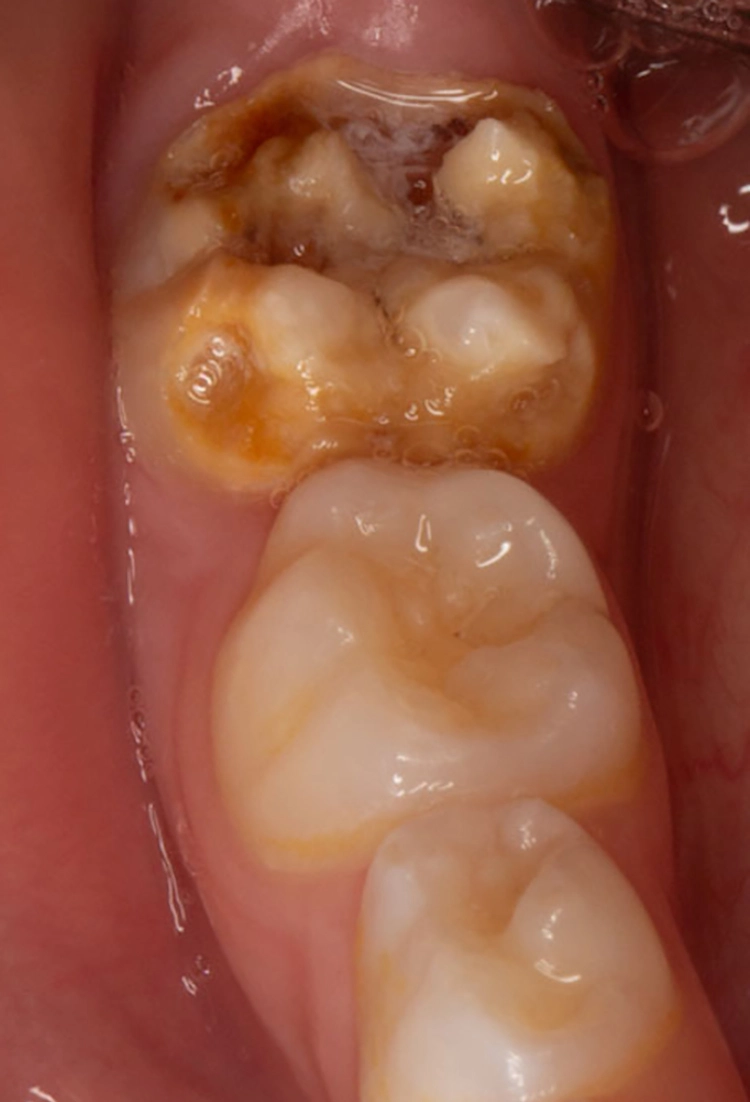

Die durch die Mindermineralisation bedingten Schmelzverluste sind meist ausgedehnt, sodass man eher selten auf approximale oder im Okklusalbereich begrenzte Kavitäten trifft, wie dies bei klassischen kariesbedingten Kavitäten oftmals der Fall ist. Bei ausgeprägten posteruptiven Abplatzungen kann es manchmal sogar zum Verlust ganzer Höckeranteile kommen (Abb. 3).

Bekes/BoukhobzaAbb. 3: MIH an Zahn 46. Typische Absplitterung des hypomineralisierten tragenden Höckers aufgrund der Kaubelastung.